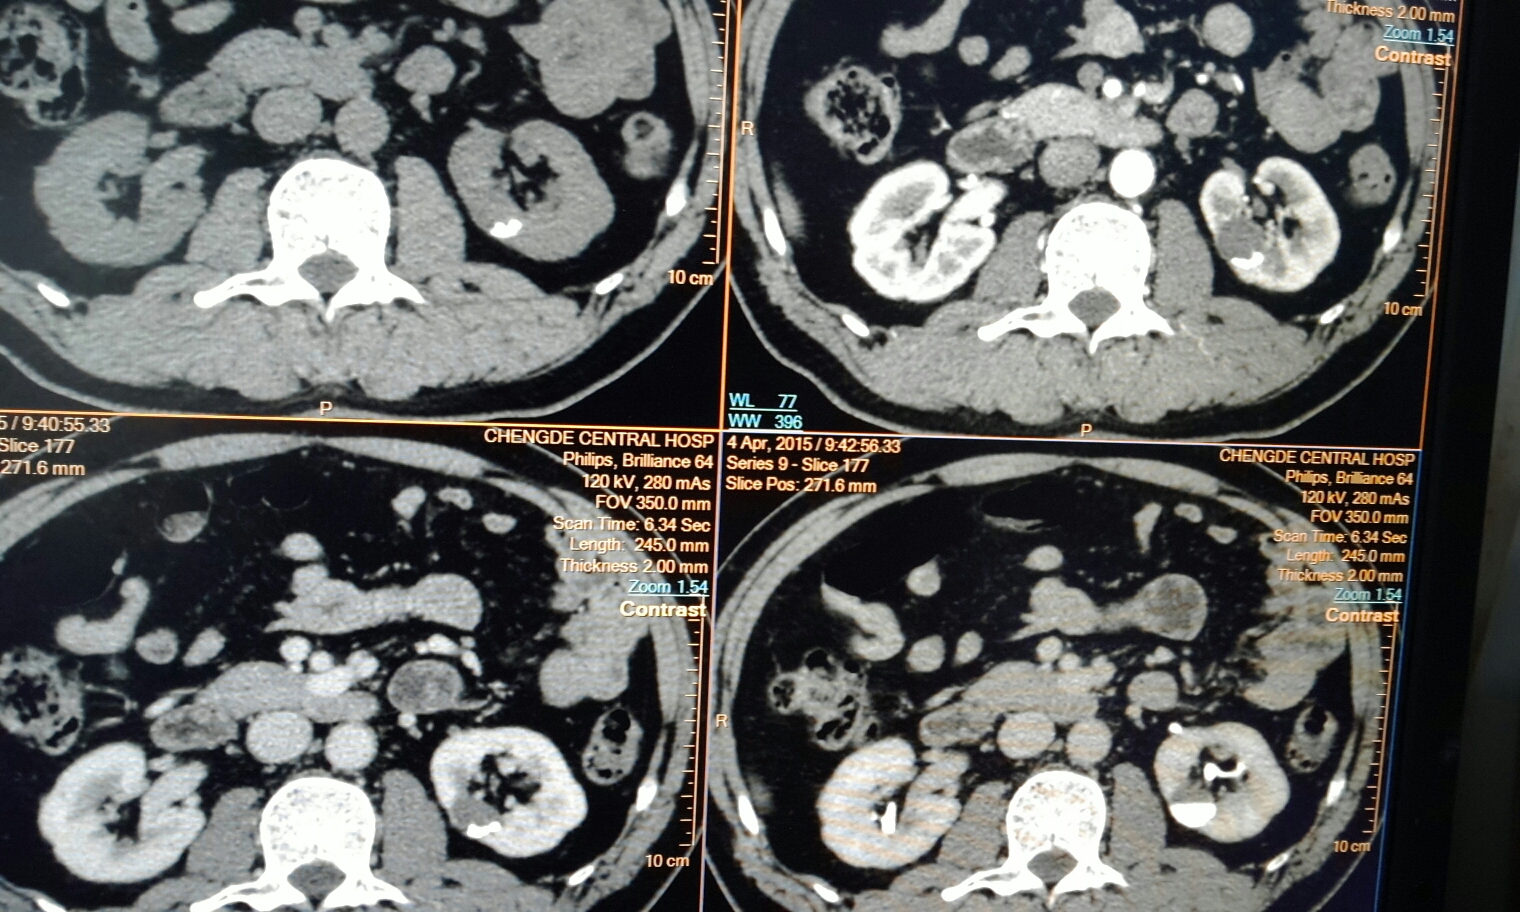

CT50192:肾盏憩室

左肾见类圆形低密度影,增强延时低密度被造影剂充填,考虑左肾憩室。

肾盏憩室。

肾钙乳-----细微的含钙颗粒呈混悬状态存留在积水的肾盏,肾囊肿或肾盏憩室内,由于含钙颗粒与混悬液之间的比重差故随体位变化而变动。

平扫肾内囊性病灶,底部可见高密度影;延迟似有造影剂进入。

没扫俯卧位